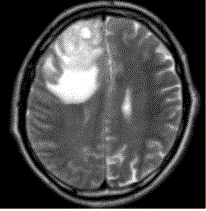

问题 患者女,67岁,头痛伴呕吐1周。既往体健。MR表现如下图。 胶质瘤术后放疗后复发与放射性坏死的鉴别手段是

选项 A.T2* B.PWI C.DWI D.Gd-MRI E.FLAIR

答案 B